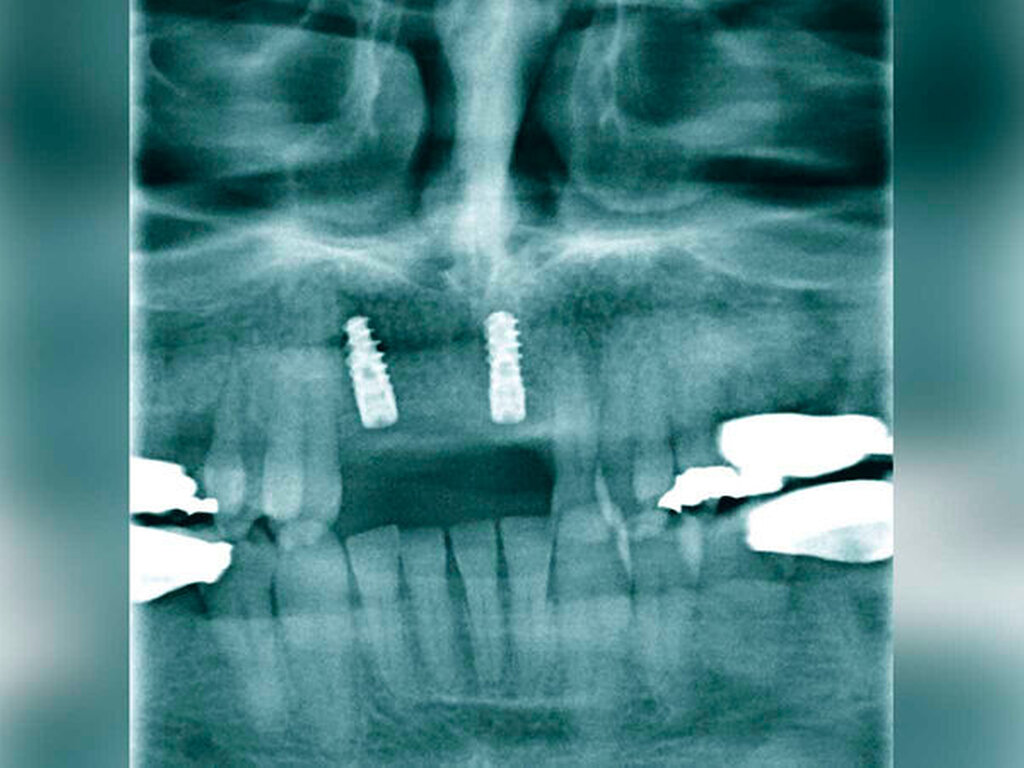

Nach sekundärer Granulation der Exzisionswunde erfolgte die Insertion von zwei Implantaten in den regiones 12 und 21 (Abbildung 5). Da eine zeitnahe Radiatio im weiteren Verlauf nicht ausgeschlossen werden konnte, wurde auf eine Augmentation des zuvor teilresezierten Alveolarkamms verzichtet, um eine festsitzende Implantatversorgung nicht zu gefährden. Weitere sechs Monate später trat erneut ein Rezidiv im Bereich des harten Gaumens auf (Abbildung 6), das wiederum ausgedehnt im Sinne einer R0-Situation exzidiert wurde. Zusätzlich wurden die zuvor inserierten Implantate im gleichen Eingriff freigelegt (Abbildung 7).